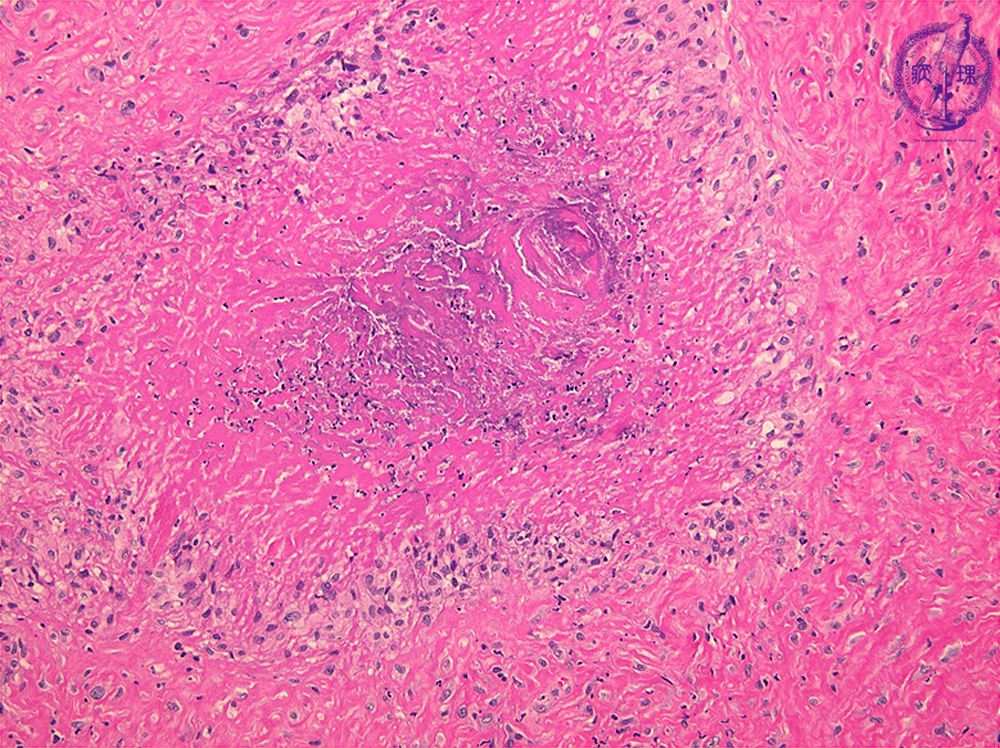

- ★(2)Rheumatoid arthritis

Microscopic view (HE; middle power view): Histology of rheumatoid nodules. These frequently occur at the subcutaneous tissue of extensor of elbow and knee, and the joint of hand, foot and fingers. Epithelioid cells are arranged at palisaded or radicular manner, and surrounding central necrosis.